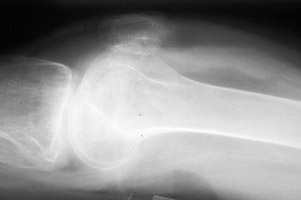

Lipohemarthrosis

Fat fluid interface seen on the multiple lateral radiographs of the knee secondary to lipohemarthrosis. The fat-blood interface (FBI) is a very suggestive sign of underlying fracture extending into the joint. If no fracture is readily identified, diligent search should be undertaken.

Cross table lateral knee - Click on the image for a larger versionACross table lateral - Click on the image for a larger versionB